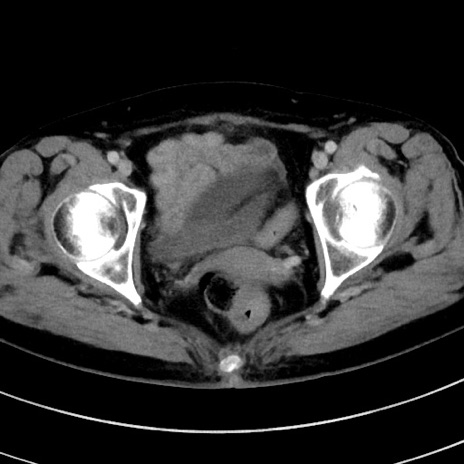

症例9(横断像)

【症例】 60歳代女性

【主訴】むかつき、みぞおちの痛み

【現病歴】3日前よりむかつきがあり、食事がとれない。

【既往歴】糖尿病

【身体所見】発熱なし、心窩部圧痛軽度あるも、腹膜刺激症状なし。

【データ】WBC 7400、CRP 1.92